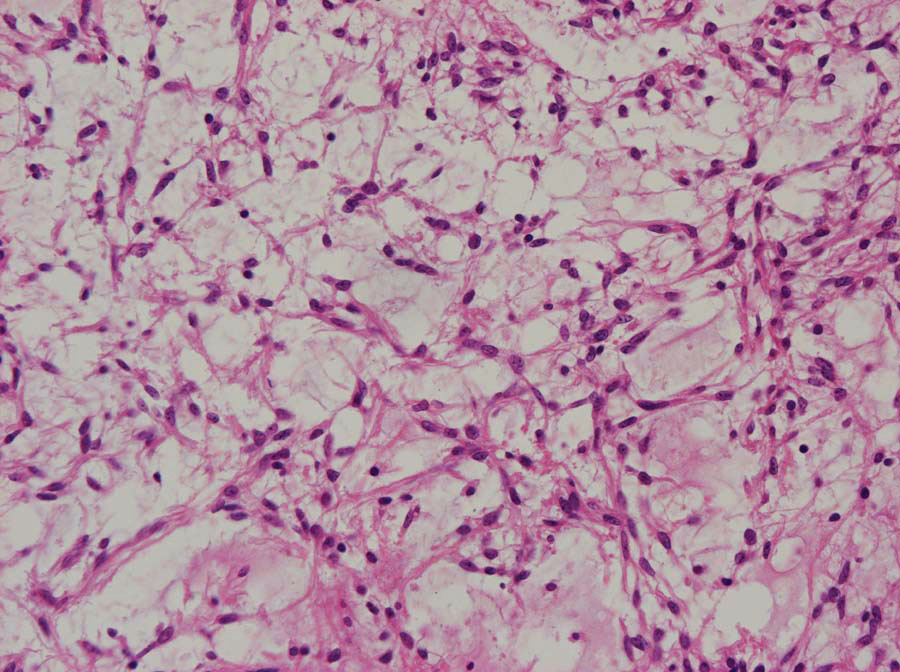

生後6ヶ月の視神経交叉腫瘍です。左では,monomorphous bipolar cellsとmucoid matrixが豊富に見られます。右では細い血管の周囲に腫瘍細胞が集簇するangiocentric patternが特徴的です。粘液性分が多くドロドロした腫瘍です。

3歳児例でのangiocentric patternで,乳児例より多少コンパクトになってきます。毛様粘液性星細胞腫においてもGFAP(右側)は強陽性です。